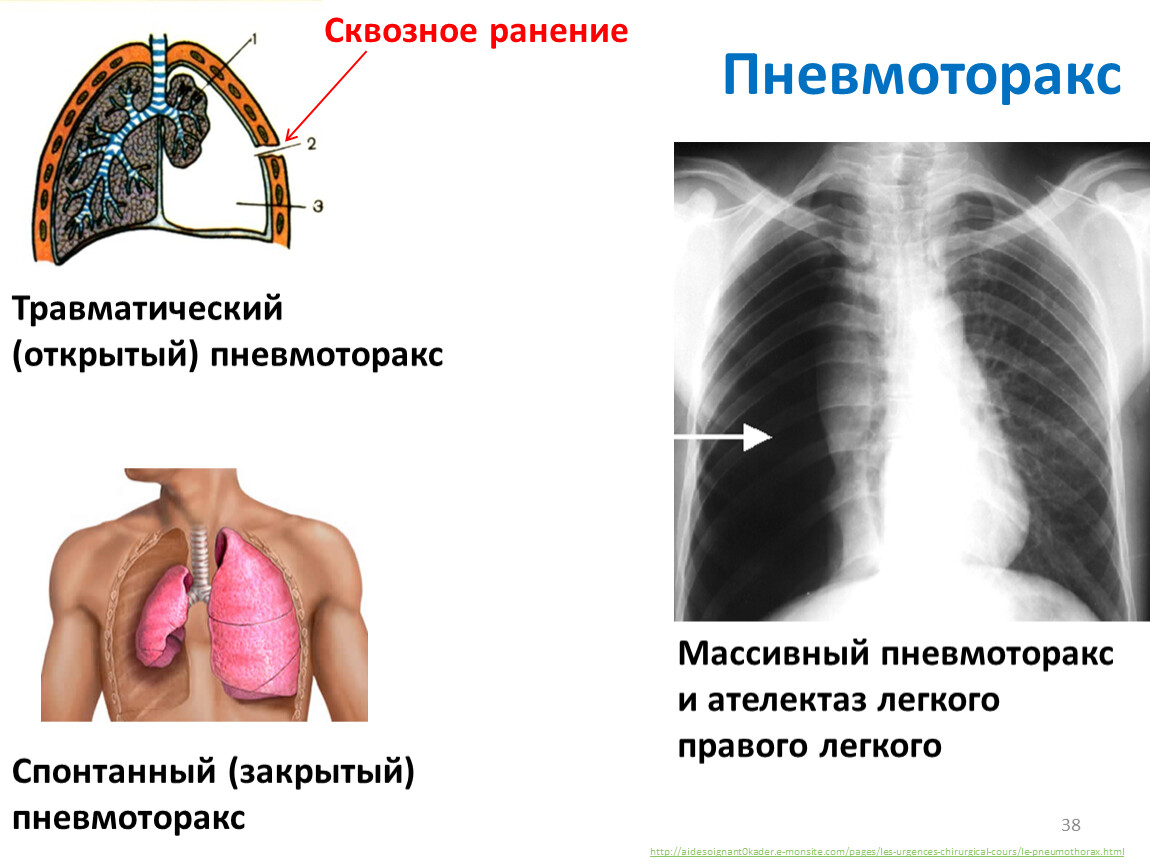

Схемы дыхания: Пневмоторакс на изображениях